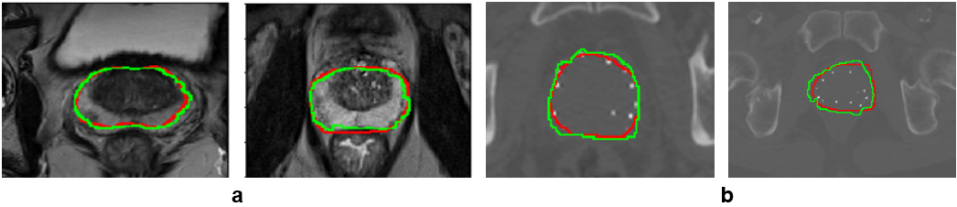

The generator was trained using a five-fold cross validation method using T2-weighted MRI. It was then kept as a shape predictor by freezing its weights during training of the proposed method. As this is an intermediate output of the method, it can be considered as a region proposal (or as instantaneous shape generator) to be further refined by merging with the encoder-decoder output. Indeed, the model-generator can learn from good contrast images (MRI) and used directly (transfer without fine tuning by freezing) for low contrast images (CT), while the encoder-decoder extracts additional features. As one can see from the qualitative prostate segmentation results in Fig. 3, the proposed method can segment accurately the prostate on both T2-weighted MR and CT images.

Refer to caption

Figure 3: Qualitative evaluation of prostate segmentation on 2D: (a) T2-weighted MRI, and (b) CT images with seeds from low-dose-rate brachytherapy. The ground truth labels are shown in red and segmentation results in green.

In almost all evaluation metrics (with and without the generator, Table 1), the proposed method with the shape model generator outperforms the state of the art methods. Since the implanted radioactive seeds were not uniformly placed over the volume of the prostate gland, it was observed to influence the segmentation quality (particularly the state of the art methods). However, they might perform better on CT images without the implanted radioactive seeds. Combining CNN-based extracted features with prior shape knowledge of the organ can improve time, reproducibility, and accuracy in fully automatic segmentation of the prostate in radiotherapy.